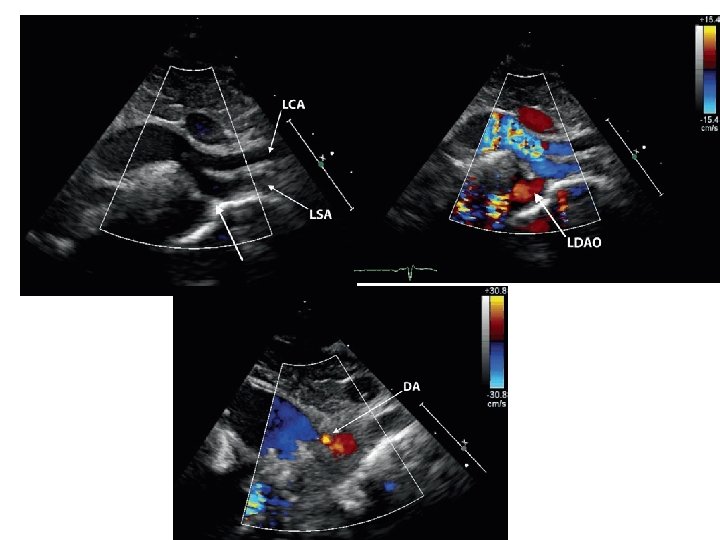

Pulmonary artery sling

• LPA arises as a branch of RPA • LPA courses in a position cephalad to right mainstem bronchus; between trachea & esophagus • Forms a "sling" and partially surrounds lower trachea • a/w tracheal stenosis • ONLY condition where a major vessel passes b/w trachea & esophagus